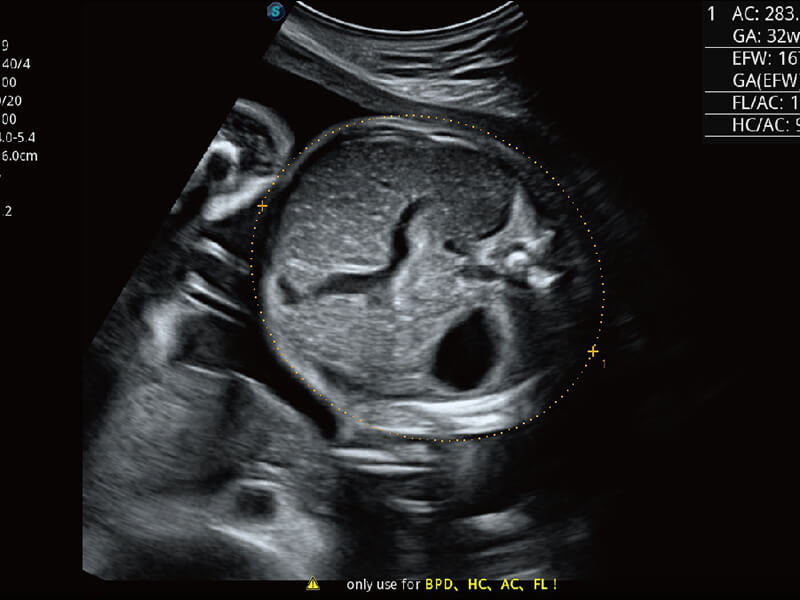

S60探头工艺,从前端信号处理每一个环节采集无损声学数据,真实还原组织原貌,再现解剖细节。

S-Fetus 产科扫查助手

准确率

按键操作